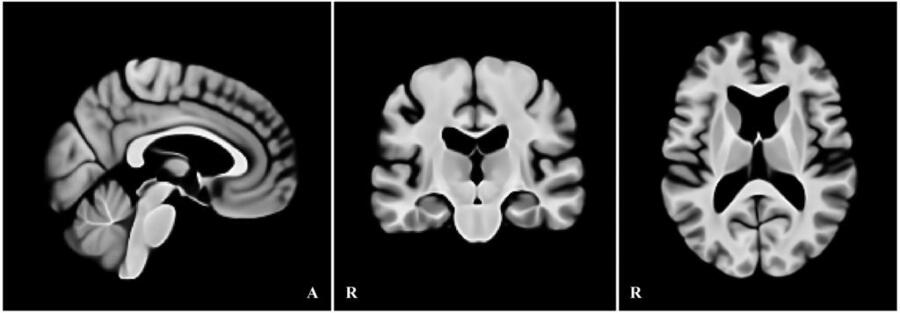

本研究では、加齢に伴う形態変化――特に拡大した側脳室や皮質の萎縮――を前提に、高齢者の脳画像を適切に基準化できる高齢者向け標準脳テンプレートを作成しました。2020年国勢調査に基づく日本の高齢者の男女比と年齢分布を考慮し、標準脳の構成が実情を反映するよう設計しています。作成データとしてOASIS-1の高齢者90例、検証データにはIXIの282例を用い、従来広く用いられているMNI152と比較しました。

検証では、IXIの各画像データを上記の手順で作成した高齢者向けテンプレートとMNI152の双方に同条件で登録し、全脳の整合(CC/MSE)と皮質下の領域(尾状核・海馬・視床・扁桃体)の一致度(Dice係数)を評価しました。その結果、60歳以降で整合が明確に向上し、CCは上昇、MSEは低下しました。特に、拡大した側脳室の位置合わせが安定し、加齢に伴う形態をより正しく反映できることが示されました。さらに、皮質下の各領域ではDice係数が1~4%向上し、局所の位置合わせ精度も改善しました。